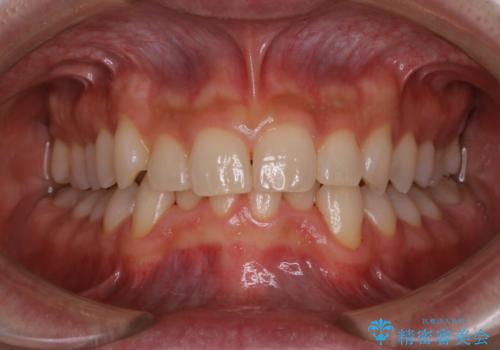

- 歯科でのクリーニングが5・6年ぶりで、全体をきれいにしたいとのことで来院されました。PMTC60分コースを行いました。

PMTCとは「Professional Mechanical Tooth Cleaning」の略で、専用の機器を使った歯のクリーニングです。

審美的面だけではなく、歯周病や虫歯・口臭などのリスクを予防することができます。